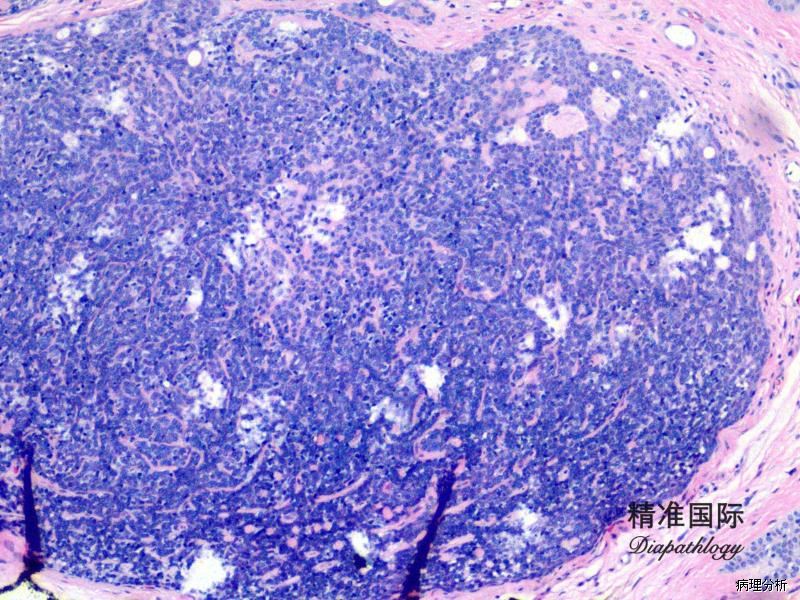

瘤体位于真皮深层,由多个或单个小叶组成,与表皮不相连,可有不完整的包膜;

小叶周边细胞体积小,基底细胞样,胞浆少,核圆形,深染;小叶中央细胞体积大,核淡染,苍白,胞浆嗜酸性;

细胞巢内有时可见局灶或弥漫小汗腺导管结构,腔内含嗜酸性 PAS 阳性耐淀粉酶物质;

部分病例间质富于血管。